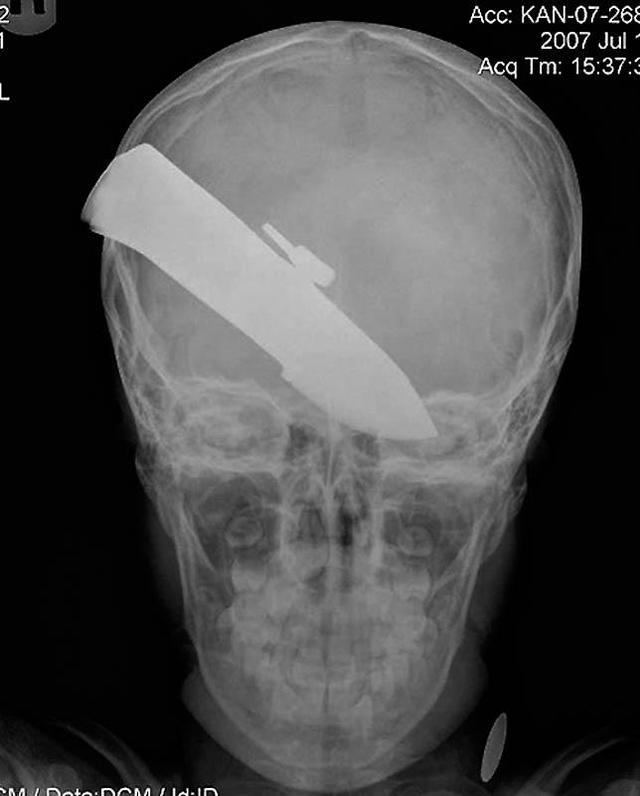

Нож в голове 10-летнего мальчика. Мальчик выжил.